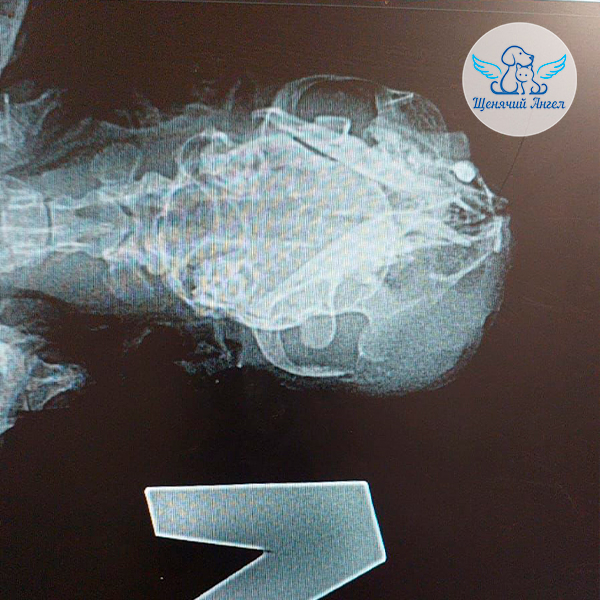

По данным первичного осмотра и рентгена 🩻 врачи выявили плотное образование в левой стороне верхней челюсти. При пальпации гной выходил через ротовую полость, подчелюстные лимфоузлы были воспалены. Врачи заподозрили новообразование 😔, а также отметили серьёзное поражение верхнего нёба.

В клинике «Зоовет» 🏥 кошечку повторно осмотрел хирург, а также ветеринарный онколог 👩🏼‍⚕️👨🏻‍⚕️, которые подтвердили обширный опухолевый процесс с выраженной деформацией верхней челюсти, участками некротизации и разрушением прилегающих тканей. Предварительно врачи предполагют плоскоклеточную карциному 😢.